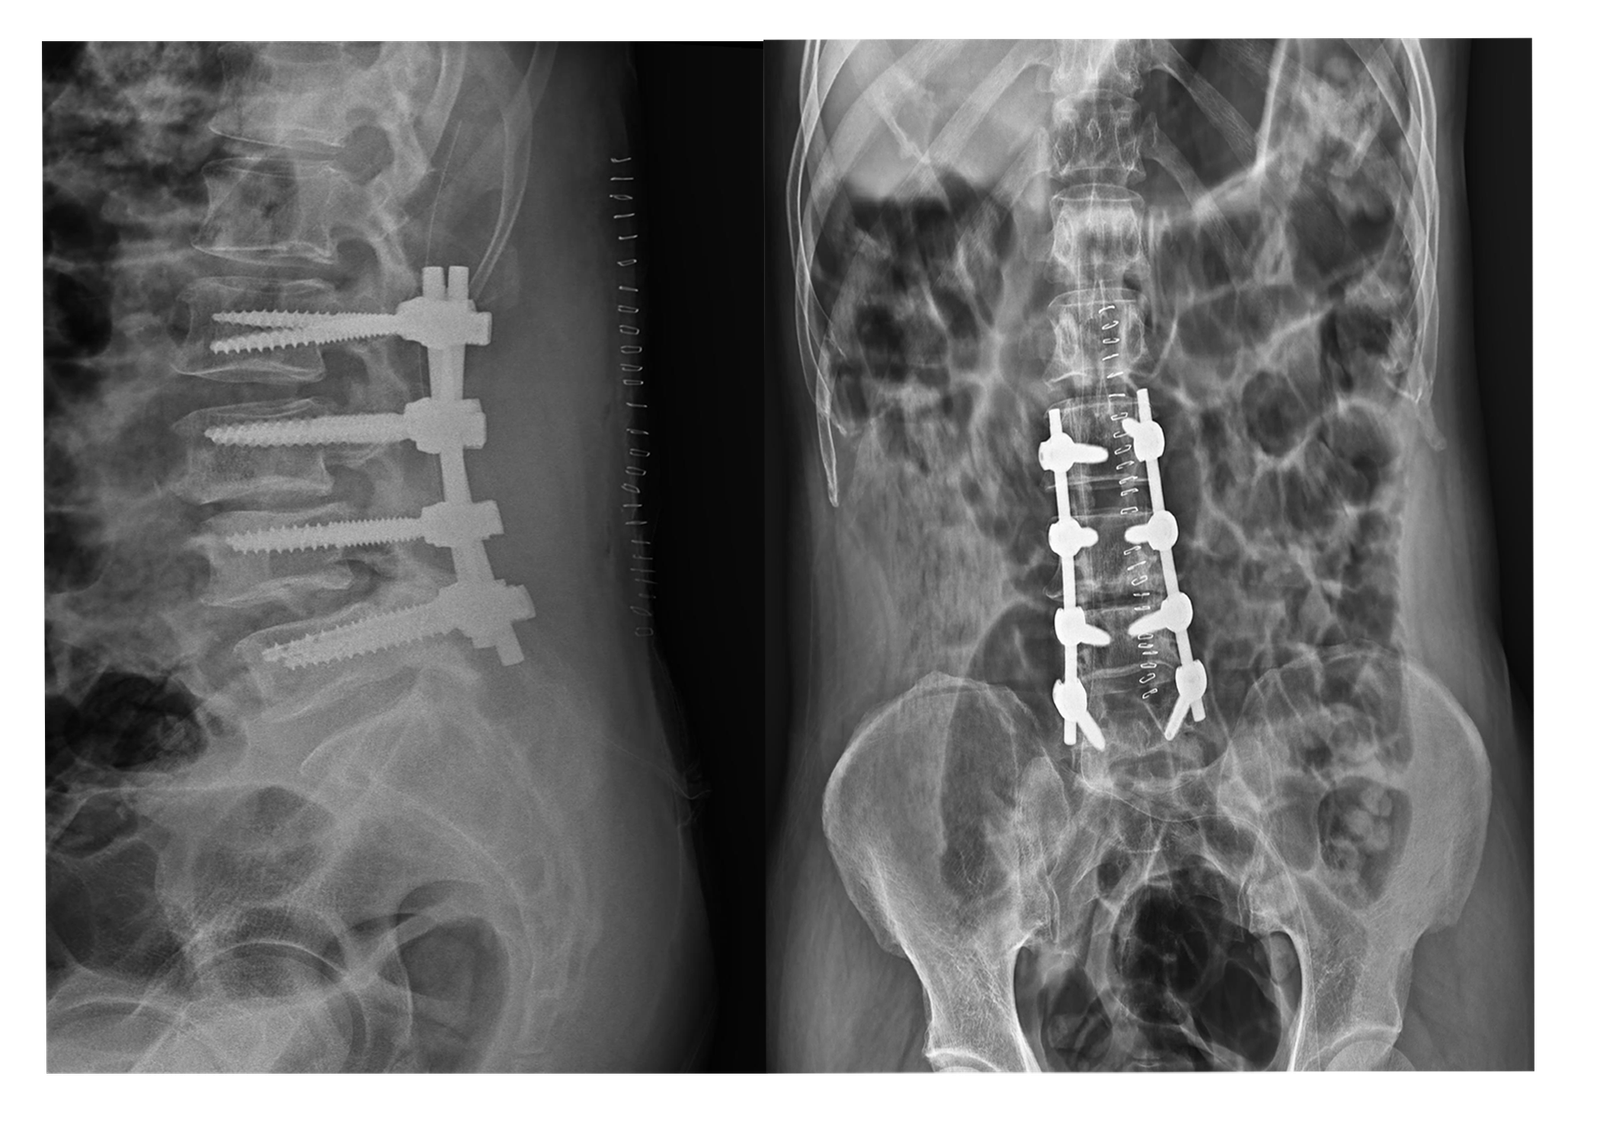

X-Rays